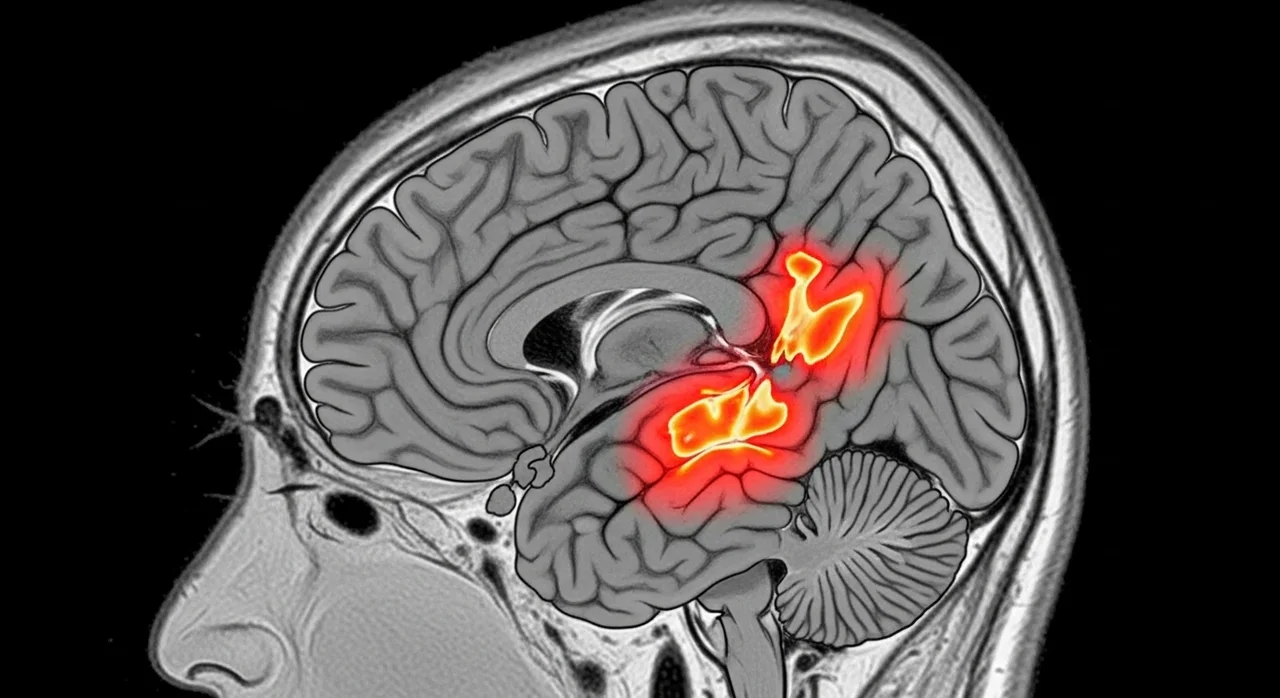

전체 치매 환자의 약 70%를 차지하는 알츠하이머는 뇌 속에 나쁜 단백질이 쌓이면서 뇌세포가 서서히 죽어가는 병입니다. 처음에는 단순히 건망증처럼 보일 수 있어 방치하기 쉬운데요.

혈관성 치매는 뇌혈관 질환에 의해 발생합니다. 뇌경색이나 뇌출혈로 인해 뇌 조직이 손상되면서 인지 기능이 떨어지는 것이죠. 특히 당뇨, 고혈압, 고지혈증이 있는 분들에게 위험도가 높습니다.